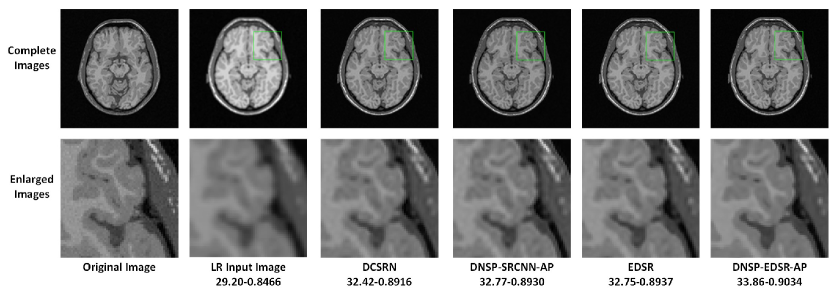

Refer to caption

Figure 11: Comparisons of top 4 methods for an image in BW data set for scale factor of 2. A small portion of the images (marked by green box) in the first row is zoomed in and shown in second row. The numerical figures constitute the respective PSNR-SSIM values.

IV-C Comparisons Against State-of-the-Art Methods

Table II shows PSNR and SSIM values for all competing methods. Note that we used two different base networks for DNSP: 1) DNSP-SRCNN-AP - the base network is SRCNN and 2) DNSP-EDSR-AP - the base network is EDSR. Three trends emerge from the results: 1) DNSP-EDSR-AP outperforms the competition, 2) DNSP-SRCNN-AP does better than all the methods except EDSR, and 3) overall, deep SR methods, i.e. SRCNN, EDSR, DCSRN and DNSP perform better than other alternatives. To confirm this statistically, we performed a 2-way Analysis of Variance (ANOVA) on PSNR values for all the methods across the two datasets which is illustrated in Fig. 10. It may be inferred from Fig. 10 that deep learning methods are statistically well separated from the traditional methods and further DNSP-EDSR-AP is well separated from all the competing methods indicating the effectiveness of using prior information. Figures 11 and 12 illustrate the results of the top 4 methods w.r.t. PSNR on a sample image from BW and ADNI databases respectively for a down-sampling factor of 2 while Figures 13 and 14 show results for a down-sampling factor of 4. DNSP-EDSR-AP particularly excels in recovering fine image detail (enlarged with zoom-in boxes), thanks to data-adaptive sharpness.